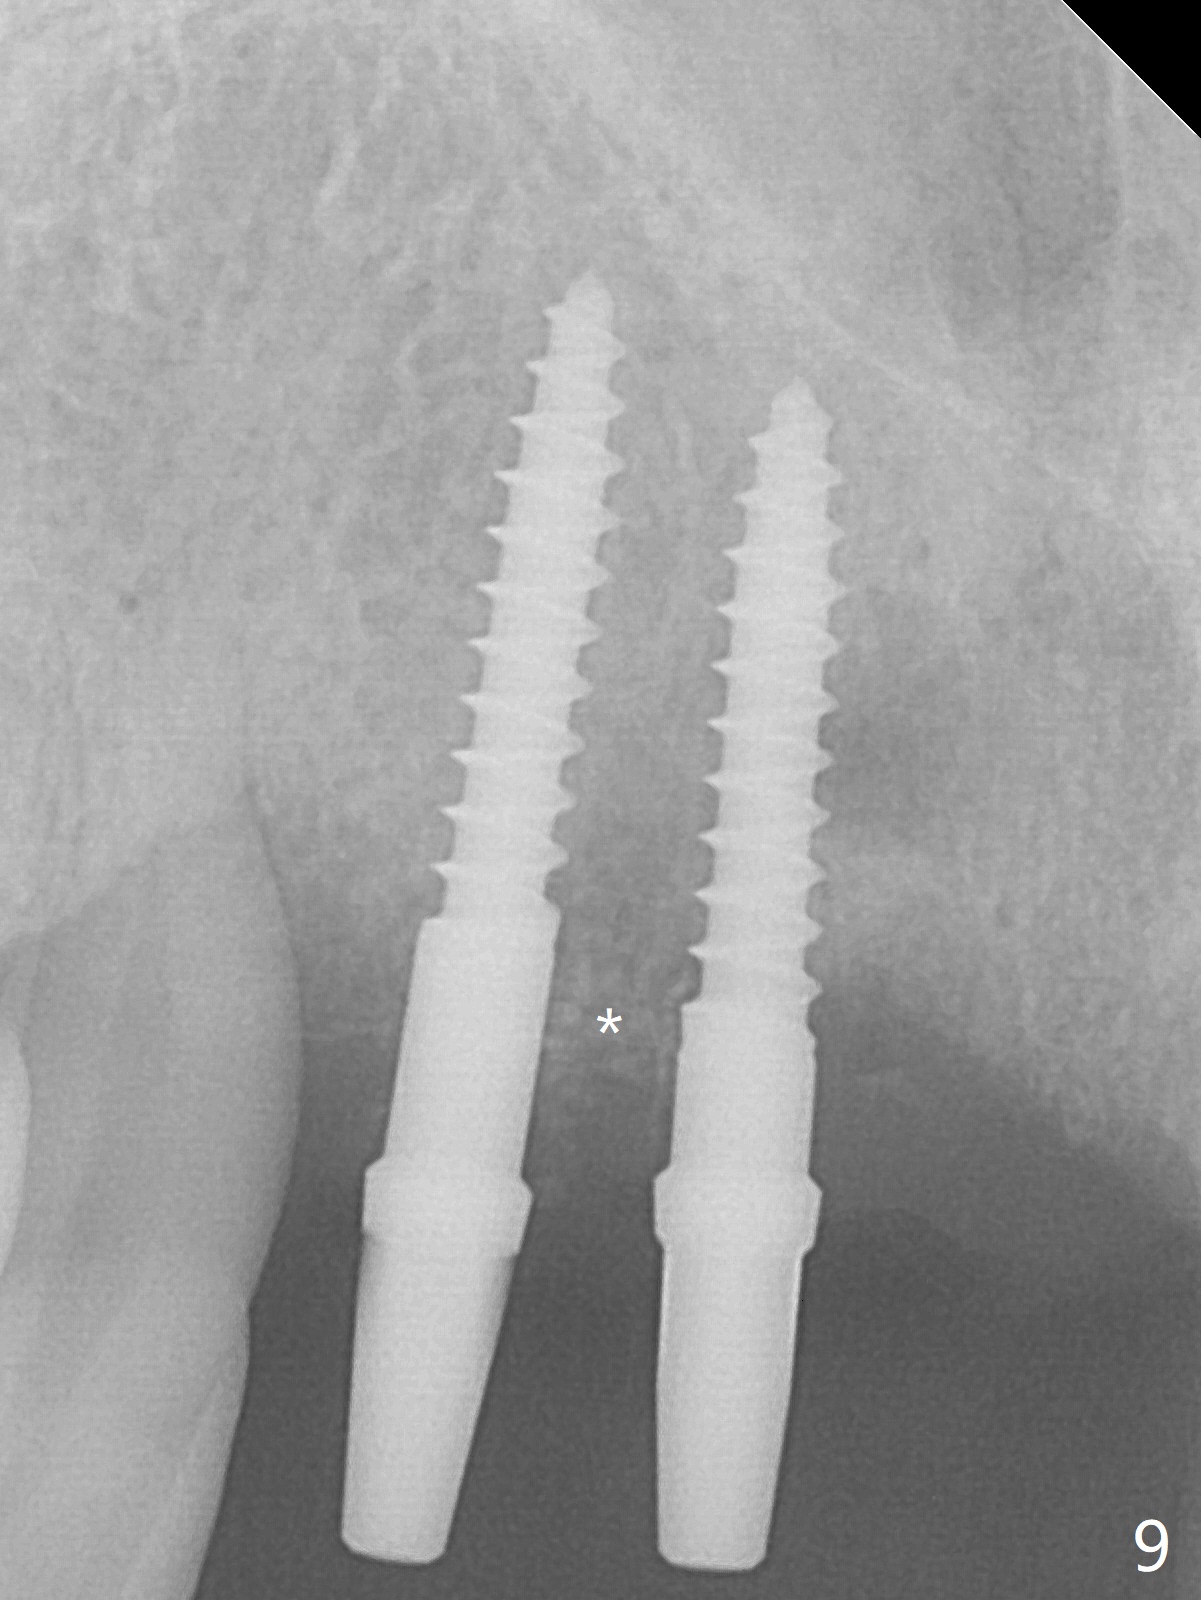

Although the ridge of the maxillary anterior ridge looks moderate in width (Fig.1), the bone is ~4 mm buccopalatally. Suction down surgical stent (Fig.2') made from the lab-fabricated provisional (Fig.2) will be used to check the position and trajectory of osteotomies. PAs taken after initial osteotomies (1.2 mm drill) show those at the central incisors tend to be mesial (close to the Incisive Canal *), while those at the lateral incisor sites distal (Fig.3,4). After adjustment, the position and trajectory of the osteotomies are acceptable (Fig.5,6). To reduce the chance of perforating the Incisive Canal (Fig.3,4 *), 2.5 mm 1-piece implants are inserted with >40 Ncm (Fig.7,8). After deep placement of the implants, Vanilla graft is placed at the crest (Fig.9,10 *). An immediate splinted provisional is fabricated from the suction down stent. The gingiva is healthy around the provisional (Fig.11) and the implants (Fig.12,13) 1 month postop. The provisional is adjusted monthly so that the interdental papillae can be elongated. No bone resorption is observed 6 months postop (Fig.14,15). Crowns are cemented 8 months postop (Fig.16-18). The keratinized gingiva appears to have formed the abutments 8 months postop immediately pre-cementation (Fig.19).